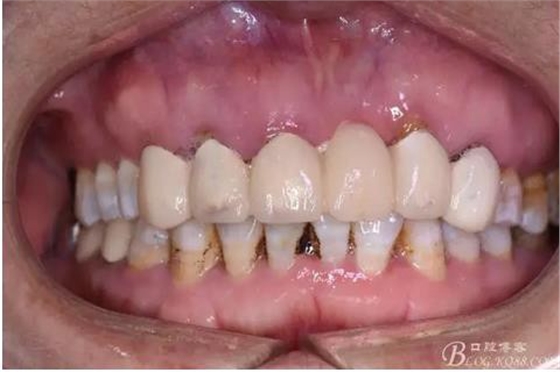

圖3.術(shù)前口內(nèi)正面照:12前庭溝輕度捫痛、有乒乓感